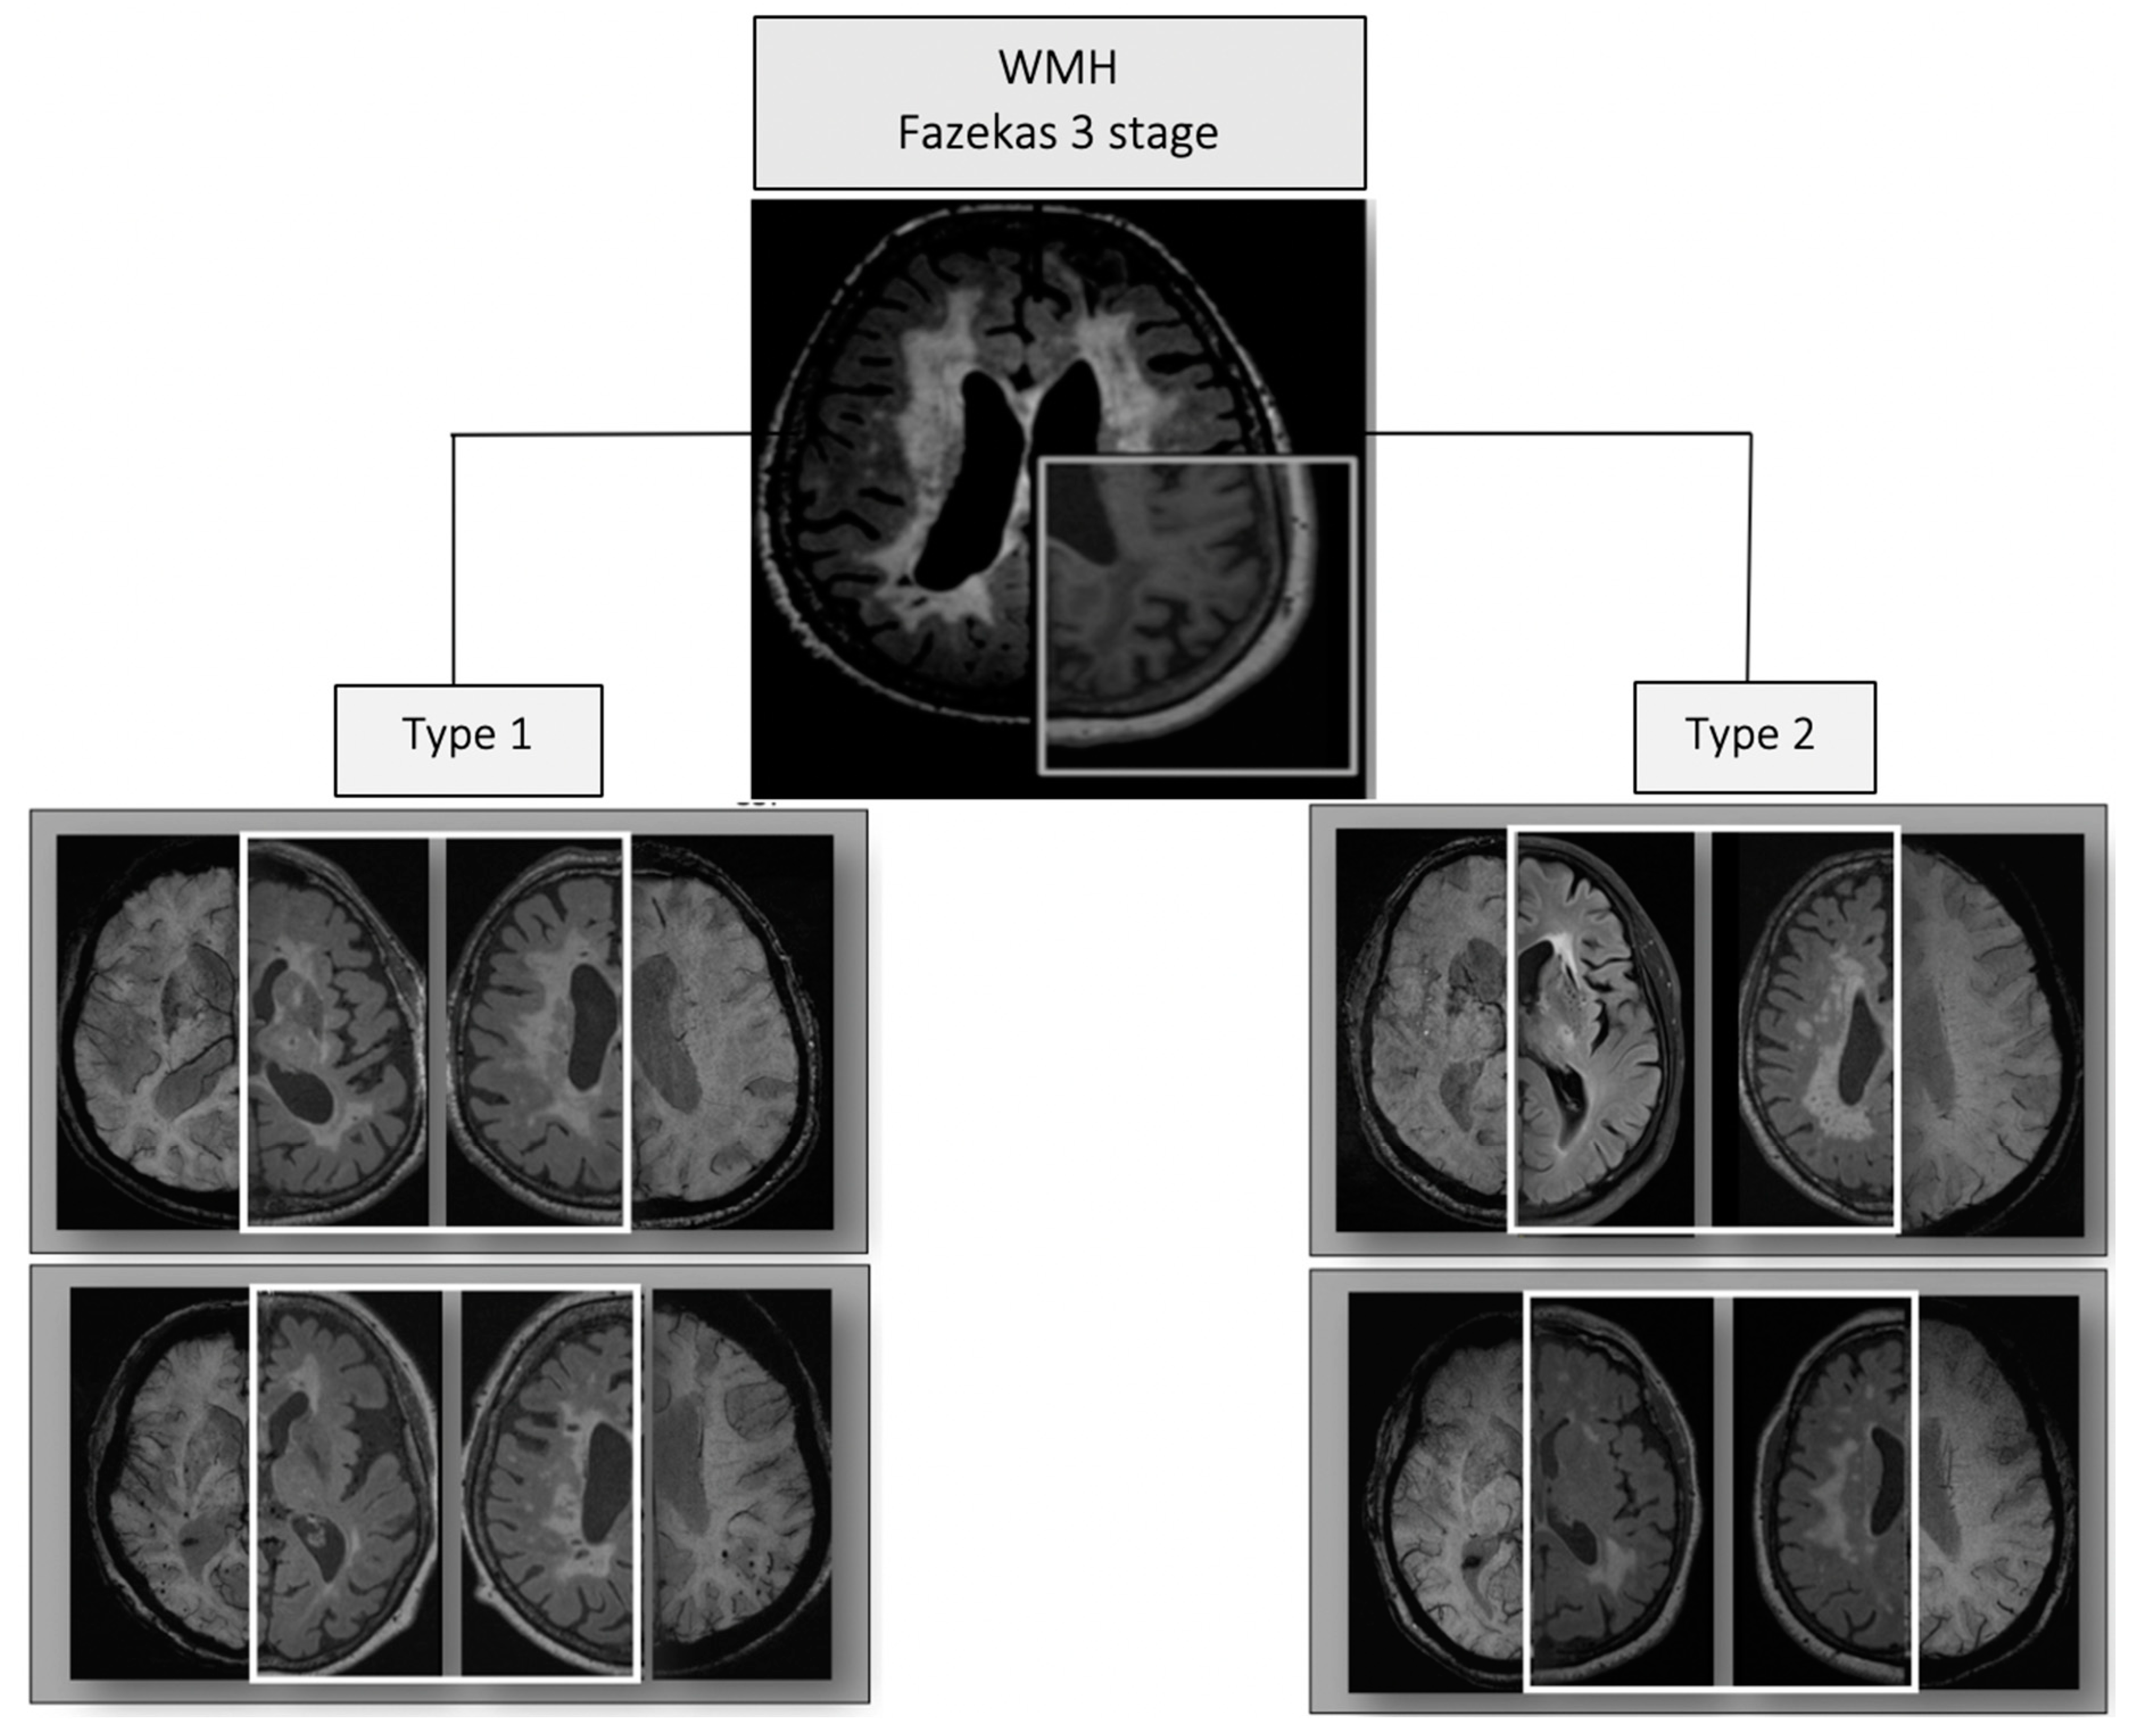

| White matter hyperintensities (stages): F1/F2/F3 | 26 (27.1%)/31 (32.3%)/39 (40.6%) |